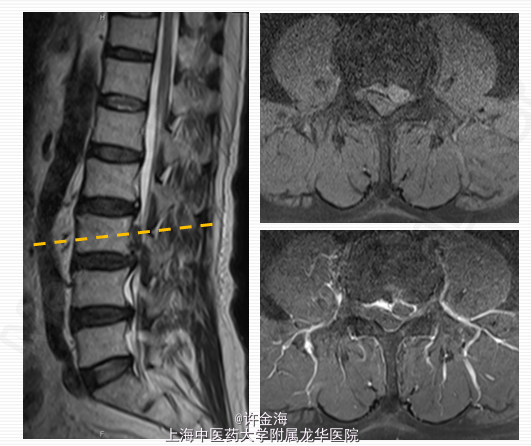

主诉:腰痛伴右下肢放射痛1天 病史:患者腰部疼痛三月,1天前腰部扭伤后出现右下肢放射痛

检查:推入病房,腰部活动受限;腰椎生理弧度变直,L3-4椎旁压痛、叩痛;直腿抬高试验右侧<30 °,加强试验(+),左侧>70;双下肢肌张力正常,右侧股四头肌肌力V-;右大腿外侧浅感觉减退;右侧膝腱反射(+),踝反射(++);髌、踝阵挛(-),Babinski征(-)。 评分:腰VAS7分;VAS腿8分;JOA10分

2周后评分:腰VAS2分;腿VAS2分;JOA22分 出院后续治疗:服用中药3月;电针、艾灸每周1次 5月后随访: 复查MRI:游离椎间盘消失 评分:腰VAS0分;腿VAS1分;JOA26分 体检:腰部活动正常,双下肢直腿抬高试验>70°,肌力V级,浅感觉正常,膝踝反射(++),病理征(-)。